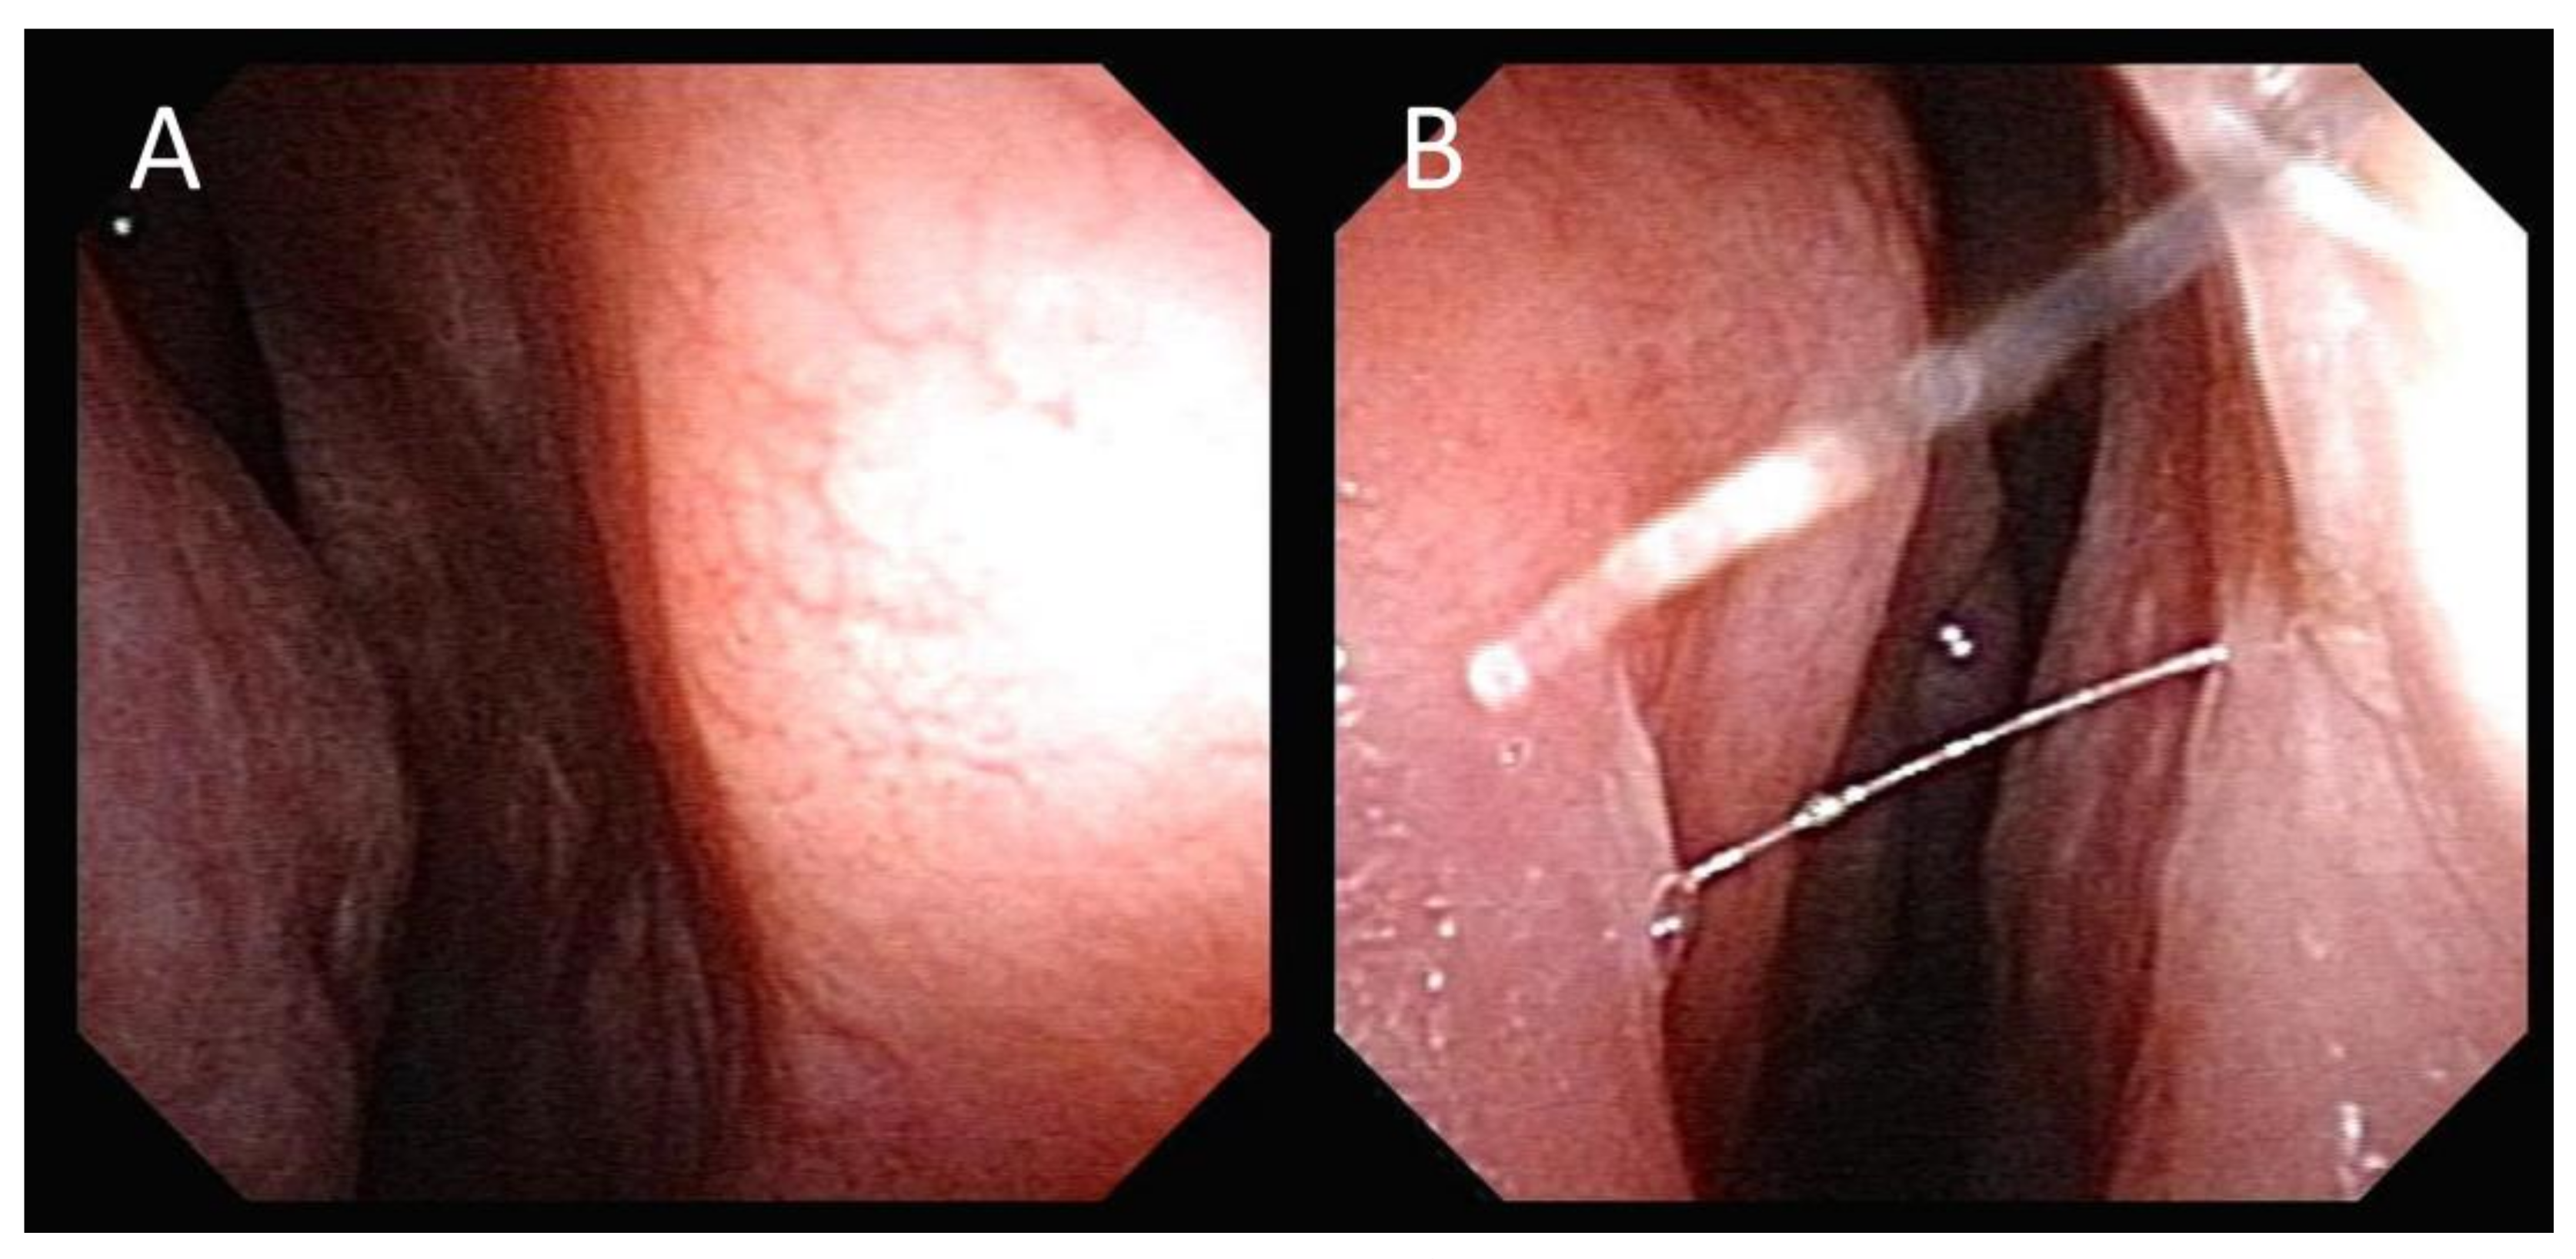

2. Case Presentation